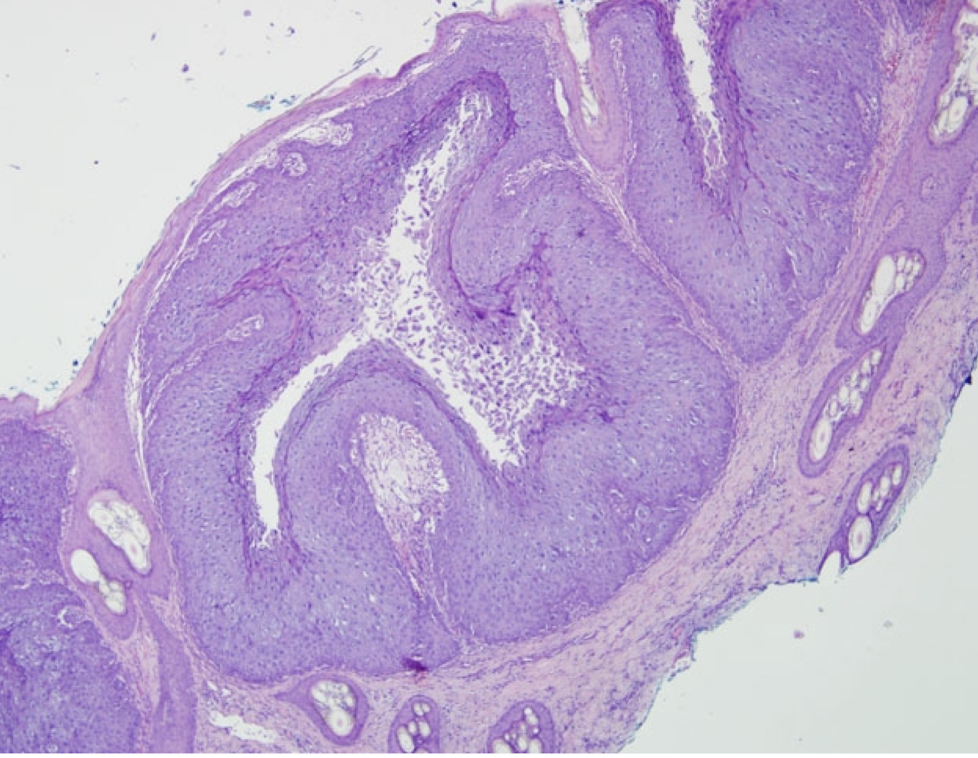

What 3 viruses cause epidermal proliferation?

A

1. Canine Distemper Virus (hyperkeratosis of nose & footpads)

2. Papilloma Virus

3. Pox Virus

VF & pathogenesis of papilloma virus?

VF = Non-enveloped

Pathogenesis = Virus replicates in nuceli of basal cells of host’s epithelium -> proliferative warts -> spontaneously regress after weeks-months w/ development of cell-mediated immunity

Lesion locations, signalment and characteristics of Canine Oral Papillomas

Lesions: oropharyngeal region (can also occur on conjunctiva, eyelids, muzzle)

Common in young dogs

Spontaneously regress in months